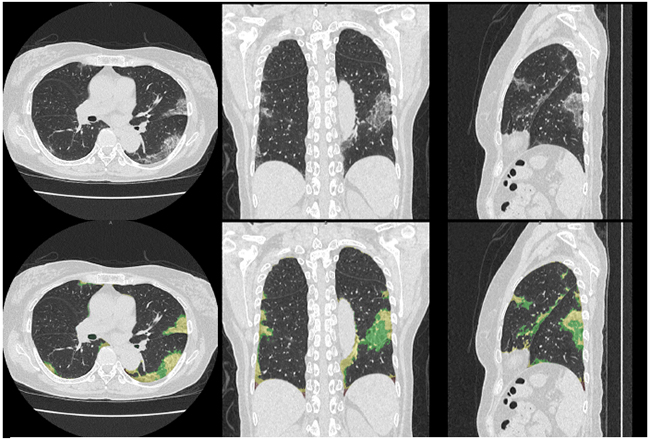

新型コロナウイルス肺炎のCT診断画像及びその解析結果(上段 原画,下段 解析結果)

今回の適用評価で用いるびまん性肺疾患を中心としたCTテクスチャー解析は,藤田医科大学 大野良治教授とキヤノンメディカルが産学共同研究で開発した技術である。本解析技術は,CT画像を用い,様々な肺疾患の結果生じる肺の陰影・形状情報から,正常肺,すりガラス影,浸潤影,蜂巣肺,粒状影や気腫性病変など,肺の7種類の形態的特徴を,機械学習によって識別し定量化するものであり,基礎的な研究成果はすでに各種学会で報告され,間質性肺炎の重症度と解析による定量的な結果に相関があること発表実績1)2),放射線科医と解析による所見の一致度が十分であること発表実績3)4)が示されている。2020年7月末から本解析技術を用いて新型コロナウイルス肺炎疑いの症例を解析し,臨床への適用評価を進めていく。

新型コロナウイルス肺炎のCT画像の所見は,間質性肺炎の特徴を示すことがこれまで多く報告されている。特にすりガラス影,浸潤影などの高濃度陰影の存在,形状および発生位置などの情報が新型コロナウイルスの診断に有用であると考えられている。新型コロナウイルスによって発生する肺炎の特徴を定量的に捉えることで,診断および治療効果,予後に寄与する情報を得られるとともに,新型コロナウイルス肺炎以外の他の肺疾患の診断をサポートする情報も得られることが期待できる。